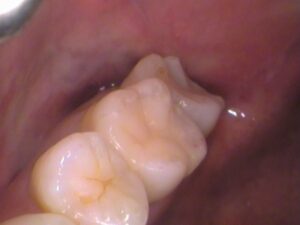

後日セラミックがセットされた状態です☟

綺麗な歯に仕上がりました(^^)/

どこを治療したのか分からないように歯の形と色を再現し、

隙間の無いようにピッタリと一体化させています。